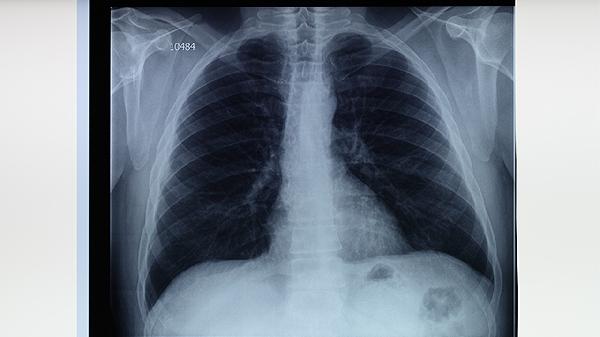

肺結(jié)核患者需避免辛辣刺激食物、高糖食品、酒精飲品、生冷食物及過量高蛋白飲食。肺結(jié)核是由結(jié)核分枝桿菌引起的慢性傳染病,合理飲食有助于輔助治療和促進康復(fù)。